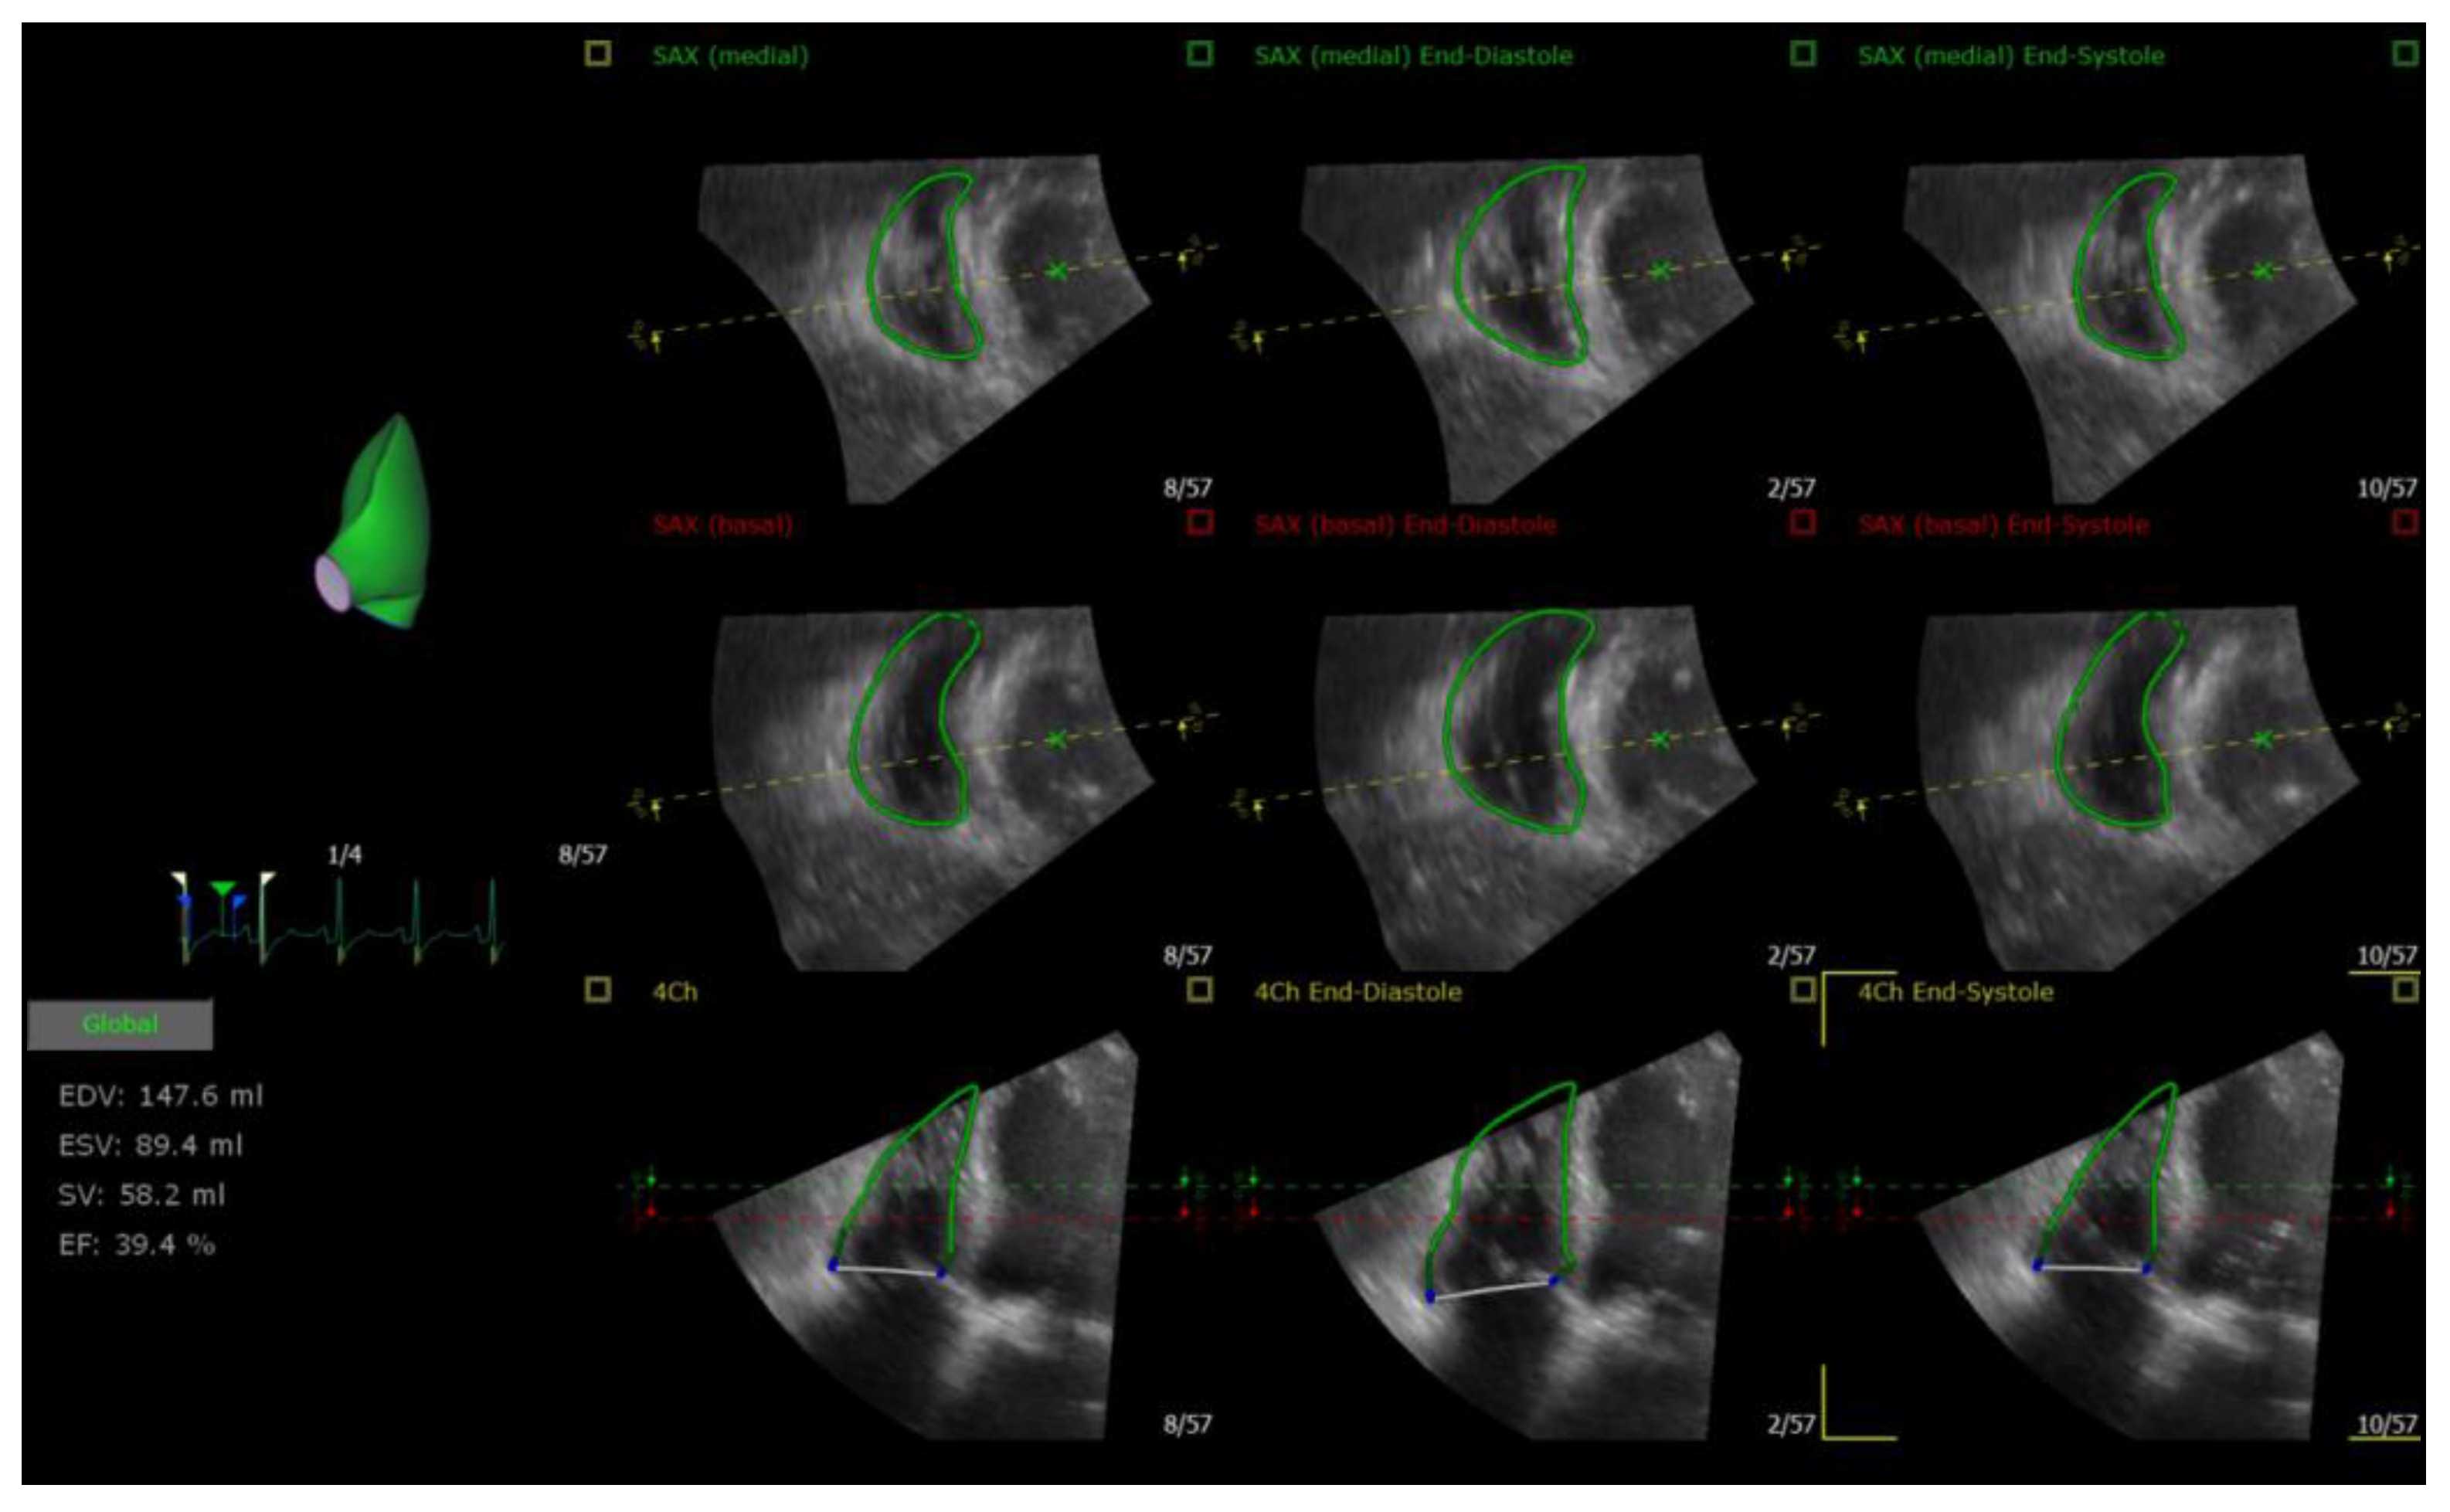

| RV end-diastolic volume, mL | 147.05 (103.08) | 182.75 (105.03) | 85.5 (86.75) | 0.007 | 0.003 | <0.001 |

| RV end-systolic volume, mL | 86.65 (65.23) | 129.5 (76.68) | 44.9 (46.9) | 0.003 | <0.001 | <0.001 |

| RV EF, % | 40.5 (6.73) | 30.85 (10.48) | 49.8 (5.85) | 0.001 | <0.001 | <0.001 |